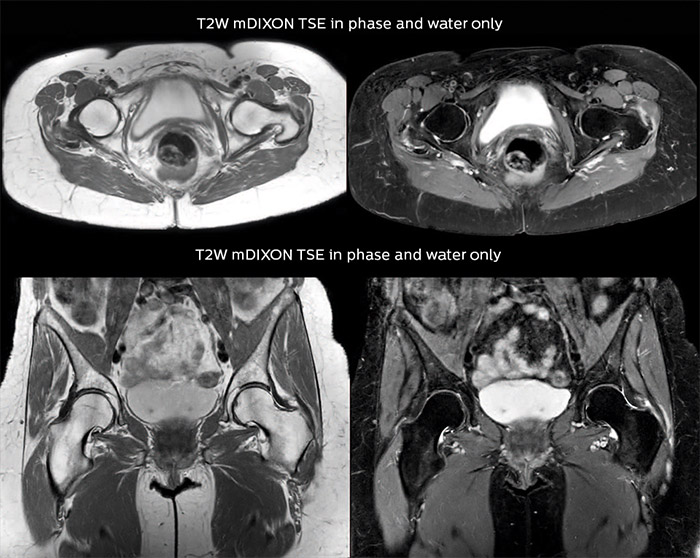

Bone assessment with confidence

“For bone assessment near joints, mDIXON TSE provides the visualization and multiple contrasts to describe abnormalities within a limited number of acquisitions. Bone marrow signal abnormalities are common MRI findings that can represent various underlying causes, from normal variance to malignancy. So, it is important for us to notice and characterize these findings. With different contrasts, both with and without fat signal as mDIXON TSE efficiently provides, we can make a confident diagnosis.”

“Other examples in bone are the signal description of a necrotic fragment in osteonecrosis, the signal description of tumoral matrix that has different components (necrosis, hemorrhage, cartilage, bone formation). These are all possible thanks to in-phase and water images from a single mDIXON acquisition.”

Spine scans must be fast and complete

“In our spine cases, we use mDIXON TSE for patients with degenerative and inflammatory spine issues, vertebral fractures and vertebral and paravertebral tumor characterization,” says Dr. Lefebvre. “It provides, in a single acquisition, different contrasts so we can both visualize and characterize spinal, focal or diffuse spine lesions.”